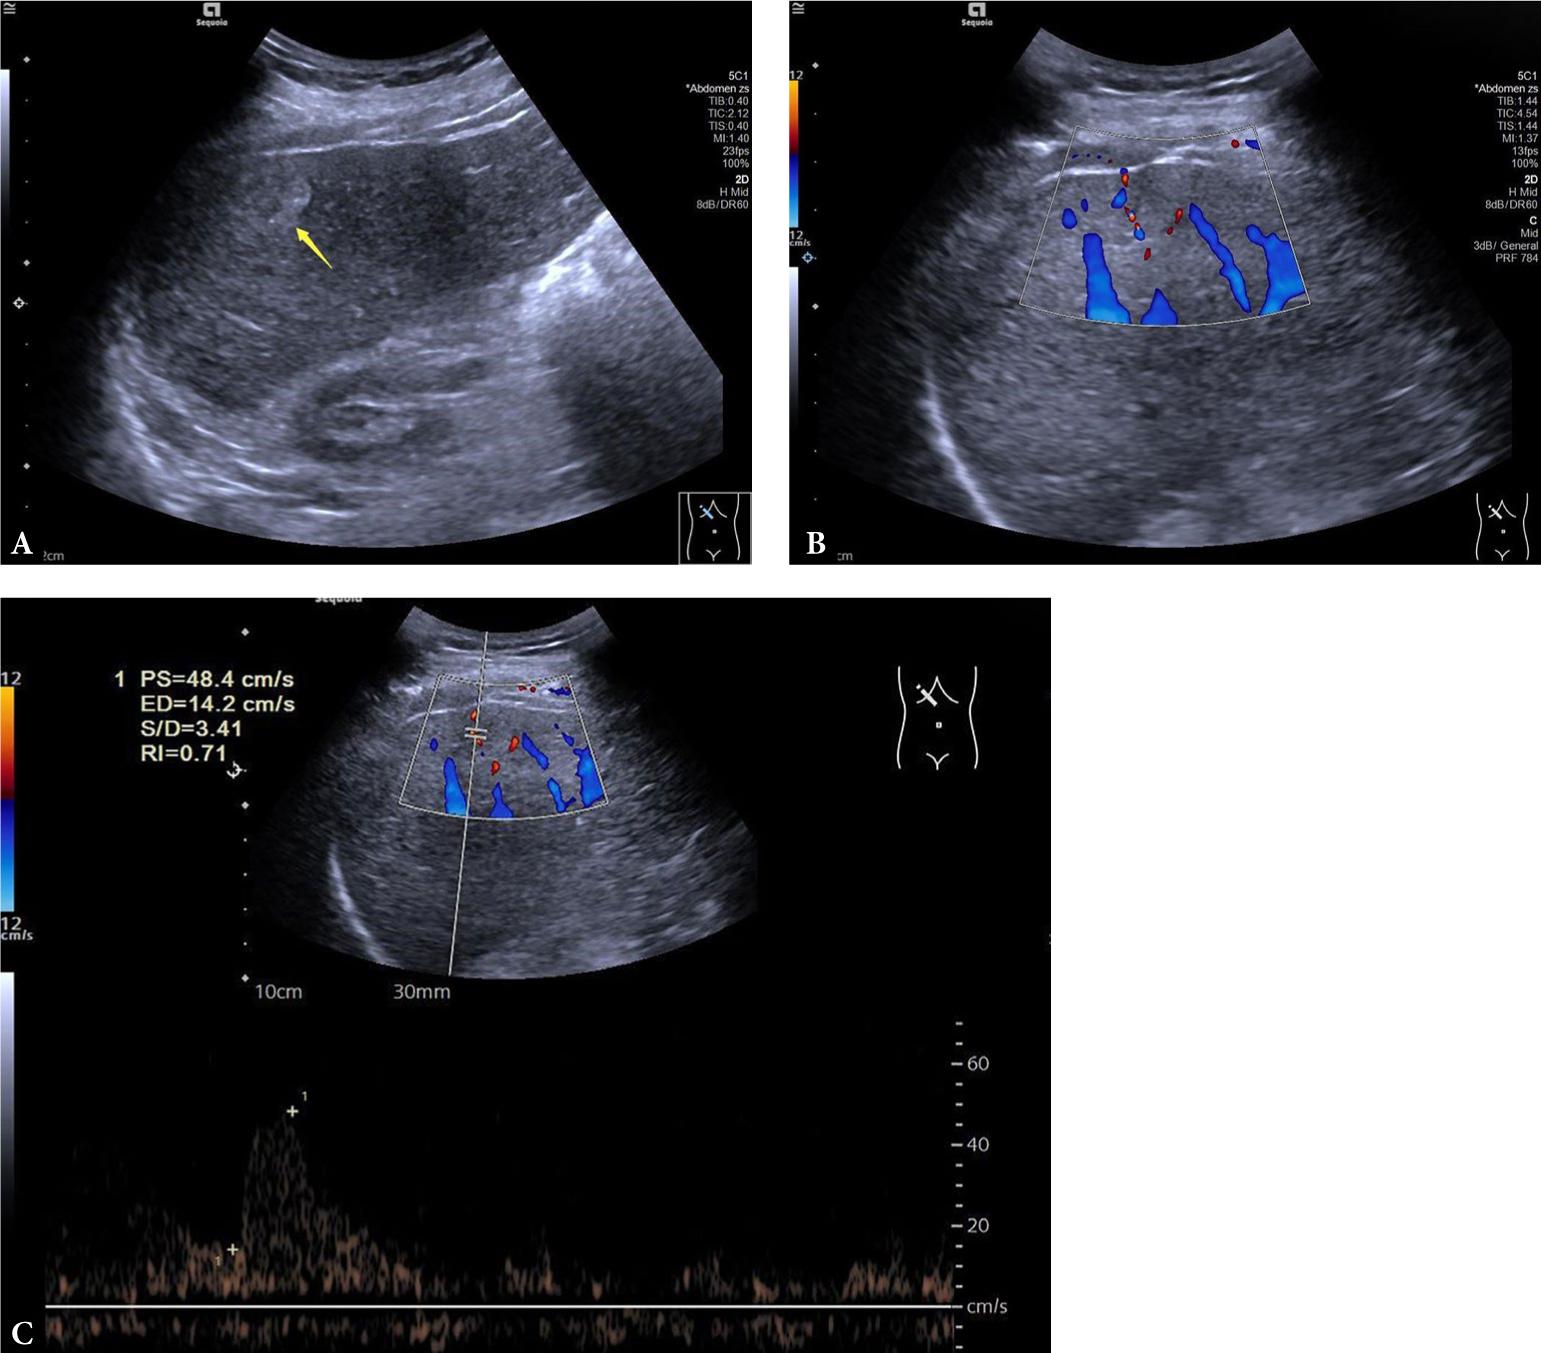

Fig. 4.